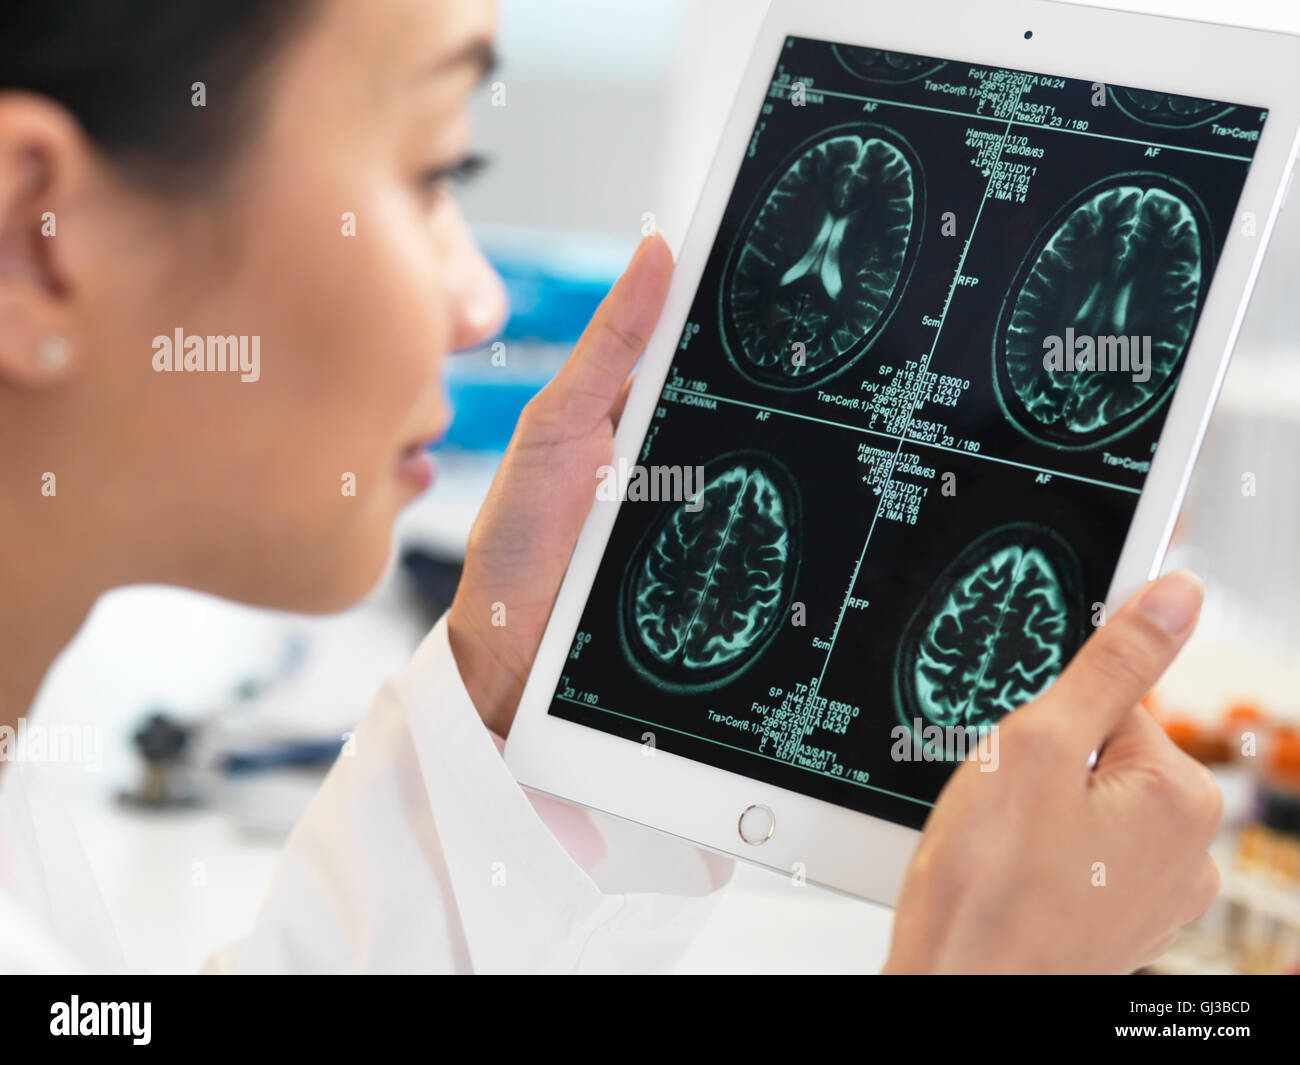

Médecin affichage CT scan suite de cerveau sur tablette numérique pour des anomalies Banque D'Imageshttps://www.alamyimages.fr/image-license-details/?v=1https://www.alamyimages.fr/photo-image-medecin-affichage-ct-scan-suite-de-cerveau-sur-tablette-numerique-pour-des-anomalies-114400845.html

Médecin affichage CT scan suite de cerveau sur tablette numérique pour des anomalies Banque D'Imageshttps://www.alamyimages.fr/image-license-details/?v=1https://www.alamyimages.fr/photo-image-medecin-affichage-ct-scan-suite-de-cerveau-sur-tablette-numerique-pour-des-anomalies-114400845.htmlRFGJ3BCD–Médecin affichage CT scan suite de cerveau sur tablette numérique pour des anomalies